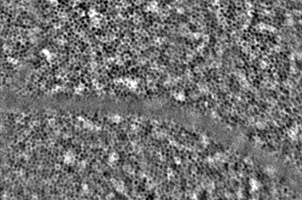

The device, developed at EPFL’s Laboratory of Applied Photonics Devices, observes changes in the RPE before the onset of symptoms, providing researchers with the first-ever in vivo images in which cells can be differentiated. Armed with this early detection capability, clinicians will be able to diagnose these disorders before irreversible symptoms occur.

Several research groups have studied these cells under the microscope – in vitro – to determine their properties and to observe the morphological changes that occur with aging but also with the onset and progression of retinal disorders such as AMD and retinitis pigmentosa. Until now, however, there has been no simple and reliable method for observing the RPE in a live patient – in vivo – for early detection and ongoing monitoring of these conditions.

The camera was then assessed in a clinical trial – led by Irmela Mantel, a physician associate at the Medical Retina Unit of Jules-Gonin Eye Hospital – designed to evaluate the device’s ability to produce clear RPE images in 29 healthy volunteers. In each case, the images generated by the camera were precise enough to quantify the morphological characteristics of the participants’ RPE cells. They were stored in a database for future contribution to medical research.